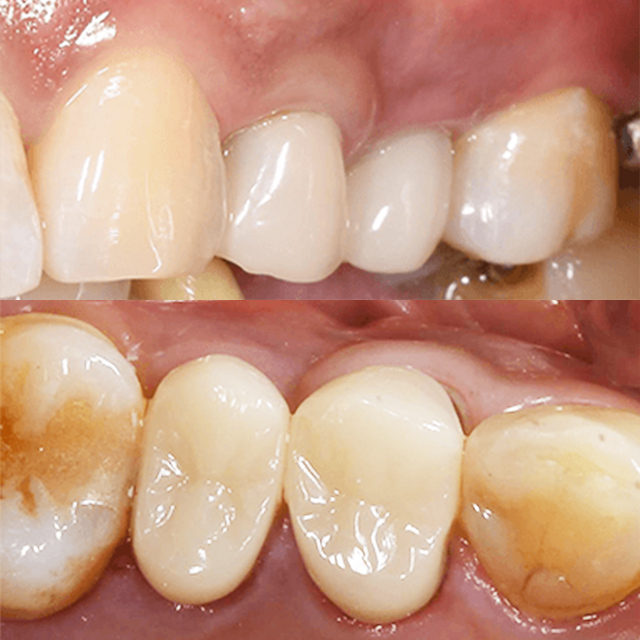

具体例です。黒くなっている部分は、神経に及ぶまでの大きなむし歯です。こちらは、むし歯治療、神経の治療を併用しました。

むし歯が大きかったのですが、保険治療のみで修復できた症例です。

症例にもよりますが、ここまでの仕上がりを実現することができました。1日で、終了しております。